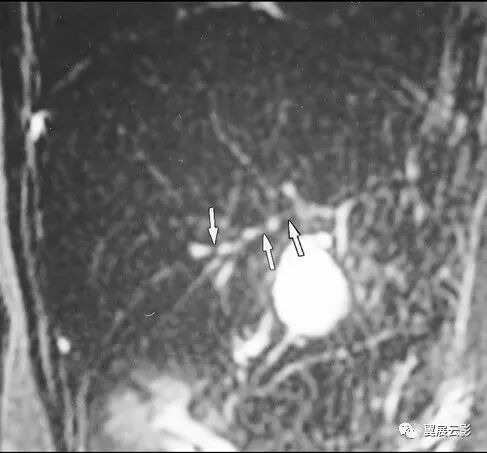

图1,2 肠系膜脂膜炎。

图1 为 MSCT平扫,显示肠系膜密度增高,CT值为 – 47 HU,与腹腔正常脂肪有清楚分界 (箭头) ,且显示肠系膜血管(箭)周围无受累,呈“脂肪环征”。

图2 为MSCT门静脉期,显示肠系膜无明显强化,CT值为 – 45 HU,与腹腔脂肪有清楚界限,形成假包膜征 (箭头) ,邻近肠管有推移改变。